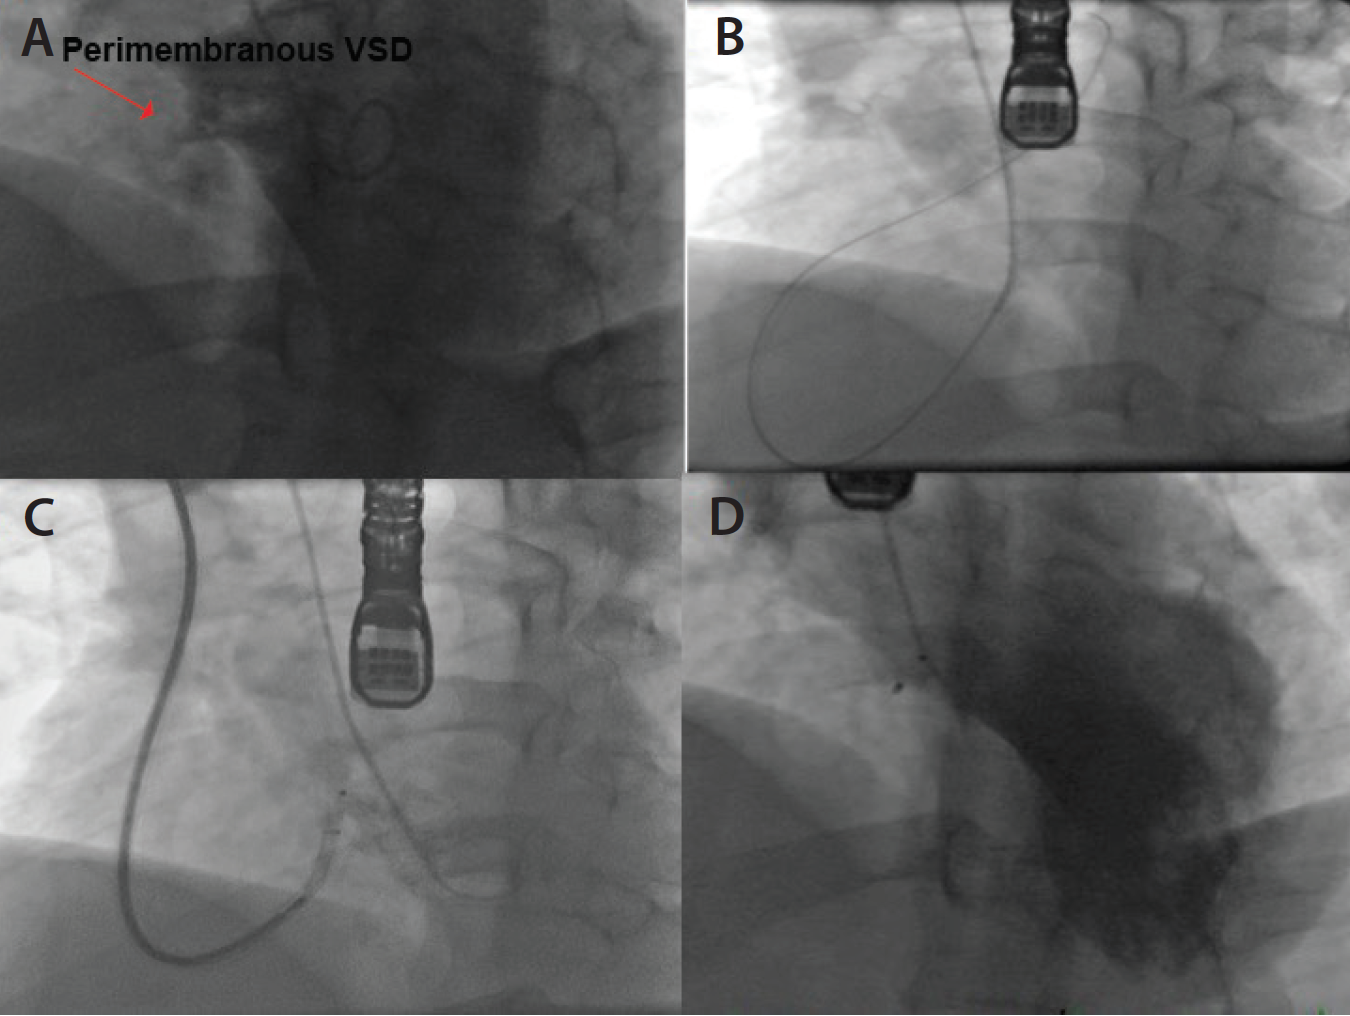

Figure 4. LV angiography showing perimembranous VSD (A). Using a JR 4 catheter from the right RA, a hydrophilic wire was crossed through the VSD into the right ventricle (B). An 8-mm Amplatzer VSD occluder was deployed across the VSD through a 6-F, 90-cm sheath that was advanced from right basilic vein access while a pigtail catheter from the right RA was inserted in the LV for ventriculography (C). Final LV angiography showing the closed VSD (D).

After the early description in 2002, percutaneous techniques and devices have been developed overtly for the closure of perimembranous VSD. Traditionally, femoral artery and vein access or jugular access have been used for VSD closure, but we reported a case of percutaneous closure of a perimembranous VSD through an arm approach (RA and basilic vein) (Figure 4).8 In our experience, crossing a high perimembranous VSD is quite easy from the RA approach using a JR 4 catheter and an angled, torqueable 0.035-inch wire. Although the access-related complications from femoral artery, femoral vein (FV), or internal jugular (IJ) vein access are arguably low, RA and basilic vein access may offer a safer access, or at least provide another alternative, particularly when access choices are limited.

In other instances, we have used a combination of radial artery and FV access or a combination of FA and AVA that can be customized for the anatomy of each individual patient (Figure 5). With the miniaturization of the device profile to a 12-mm diameter, the Amplatzer VSD occluder (St. Jude Medical, Inc.) can be deployed through a 7-F sheath. The basilic vein access is preferred over cephalic vein access. Ultrasound guidance or the levophase technique can be used to determine a fairly large superficial basilic vein.9 As the veins expand, a sheath (> 7 F) can be used through the basilic vein in appropriately selected patients, which will allow the use of a large VSD occluder.